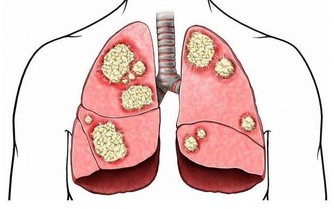

因為有了這一次治療頸椎和胸椎的經驗以後,發現很多患有頸椎病、腰椎病的人,在頸椎以下、腰椎以上相連接的椎體上,均存在著錯位,因此,得出一條重要結論:頸椎有病連著肺,腰椎有病連著胃。

這句話講的是什麼意思呢?頸七椎向下相連的是胸椎的一椎、二椎,這兩個椎體與肺相通,是通往肺的通路,當頸椎扭傷一定牽連到胸椎的一、二椎;腰椎向上相連的是胸十椎、十一椎、十二椎,十一椎、十二椎與脾、胃相通,是通往脾胃的通路,當腰椎扭傷一定牽連到胸十、十一椎。

胸椎的每個椎體,均與臟腑相通,是通往臟腑並為臟腑提供氣血的通路,當胸椎第一、二椎體發生了錯位,必然造成通往頸椎,肩膀的經脈運行受阻,氣血循環不暢,影響對頸椎和胳膊等部位的供血,導致通往頭部和肩部經絡受阻,血液循環不暢通,因而在頭部出現疼痛和胳膊發麻的病症。當錯位的胸椎經復位治療,一旦復位“開閘放水”,經脈通暢,活血化瘀,就迅速的滿足了頭部和胳膊缺血的需要,使頭痛和手指發麻的病症及時得到恢復。

胸一椎:上臂手腕指,食管氣管小魚際;心悸胸痛伴咳喘,肩臂疼痛難呼吸。

胸二椎:循腋至肘上;三至十二胸肋肌;咳嗽氣喘上臂痛,心悸心慌心胸疾。

頸椎下端和腰椎上端的這些部位,往往是在臨床中被遺忘的角落,所以,既影響頸、腰椎的治療,也影響與之相連病症的治療效果。醫者在治療頸椎腰椎的同時,一定要檢查鄰近胸椎椎體的排列狀態,頸椎的治療要注意到肺(胸一、二椎),腰椎的治療要注意到胃(胸十、十一椎),這是治療頸椎腰椎病症的關鍵。